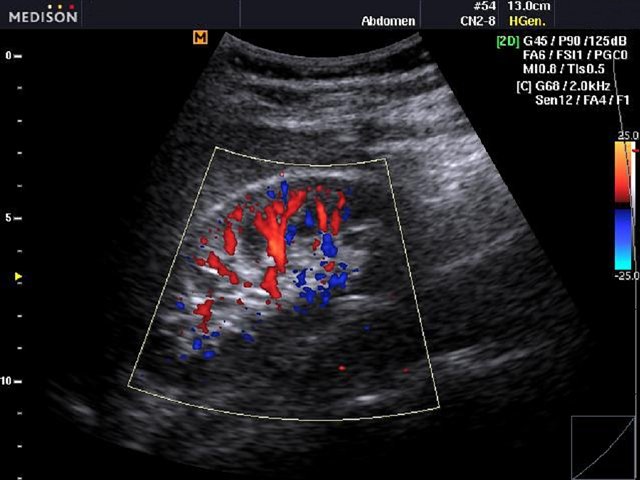

Kidney, color doppler

Kidney, color doppler (echogramm №479)

[RU] Ultrasound image №479: Kidney in color doppler mode (CFM).

Echogramm was received by ultrasound scanner SonoAce-R3 (out of production).